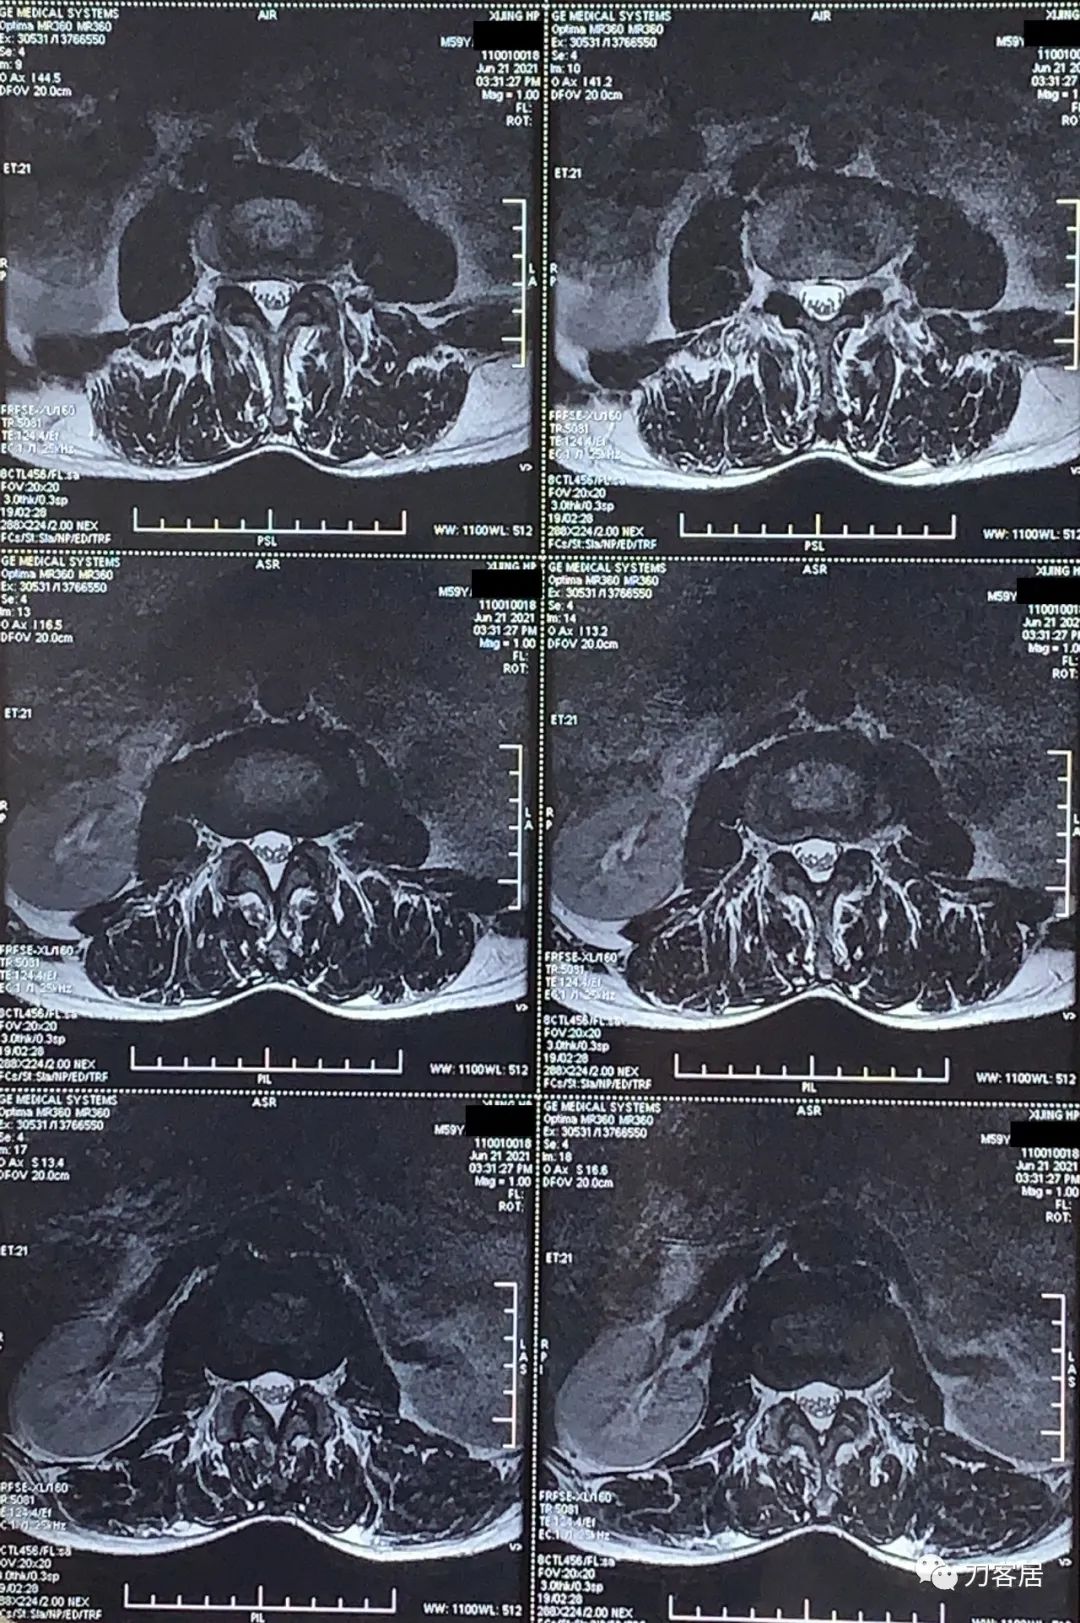

图3. 20210621西京医院腰椎MRI01

图4. 20210621西京医院腰椎MRI02

图5. 20210621西京医院腰椎MRI03

图6. 20210621西京医院腰椎MRI04

图7. 20210621西京医院腰椎MRI05